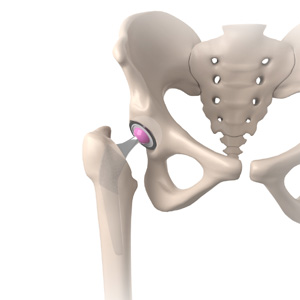

Total Hip Replacement

Total hip replacement is a surgical procedure in which the damaged cartilage and bone are removed from the hip joint and replaced with artificial components.

Hip replacement surgery is one of the most common orthopedic surgeries performed. It involves the replacement of the damaged hip bone (ball shaped upper end of the femur) with a ceramic ball attached to a metal stem that is fixed into the femur and placing a new cup with a special liner in the pelvis.

Hip replacement surgery is one of the most common orthopedic surgeries performed. It involves the replacement of the damaged hip bone (ball-shaped upper end of the femur) with a ceramic ball attached to a metal stem that is fixed into the femur and placing a new cup with a special liner in the pelvis.